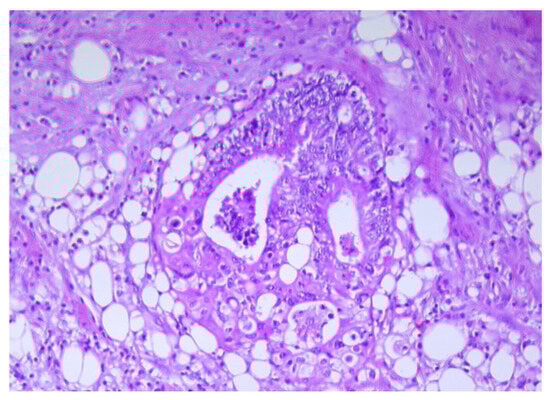

2. The Crosslink between Obesity and Colorectal Cancer

3. Cancer-Associated Adipocytes (CAAs) Characteristics

4. Potential Mechanisms of CAAs Differentiation in CRC